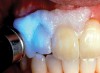

The whitening agents are available in various concentrations ranging from 10% carbamide peroxide (equal to 3.4% hydrogen peroxide) to 38% hydrogen peroxide. If the higher concentration agents contact the soft tissues, they can produce a chemical “burn” that turns the tissues temporarily white (Figure 1 and Figure 2). Although tissues quickly return to their normal color once they rehydrate, they may be mildly uncomfortable for a few hours. The patient may be distressed by the temporary appearance of the whitened soft tissues. A rubber dam or other protective barrier is mandatory to effectively seal off the tissues (Figure 3). In-office systems usually supply a light-cured resin in a syringe to apply around the cervical areas to confine the agent to the teeth (Figure 4 and Figure 5). In addition, flexible spreaders should be placed in the mouth to prevent the cheeks or lips from contacting the whitening agent.

Figure 3  Ideal rubber dam isolation should include inverting the material around the crown.